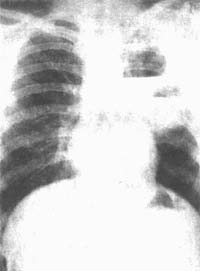

2.X線檢查

①臨床症狀與胸片所見不一致。當肺炎初起時,臨床症狀已很重,而X線徵象卻很少,僅表現為肺紋理重,一側或雙側出現小片浸潤影;當臨床症狀已趨明顯好轉時,在胸片上卻可見明顯病變如肺膿腫和肺大泡等現象。②病變發展迅速,甚至在數小時內,小片炎變就可發展成膿腫。③病程中,多合併小膿腫、膿氣胸、肺大泡。嚴重的還並發縱隔積氣、皮下氣腫及支氣管胸膜瘺。④胸片上病灶陰影持續時間較一般細菌性肺炎為長,在2個月左右陰影仍不能完全消失。

X線檢查: